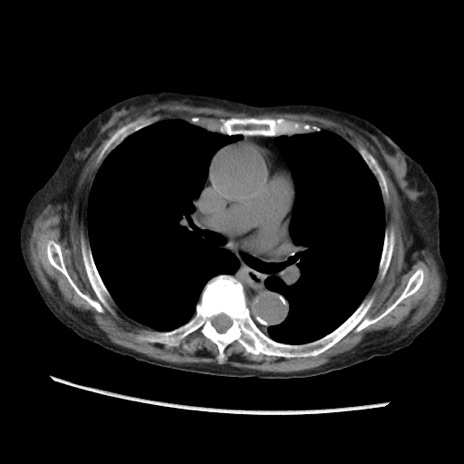

症例31(横断像)

【症例】80歳代 女性

【主訴】腹部膨満感

【現病歴】他院にて肝硬変にてフォロー中。1週間前から便秘、腹部膨満感、臍部腫瘤あり受診となる。

【既往歴】肝硬変

【身体所見】腹部膨隆あり、皮膚変化なし、疼痛なし。

【データ】WBC 4600、CRP 0.25